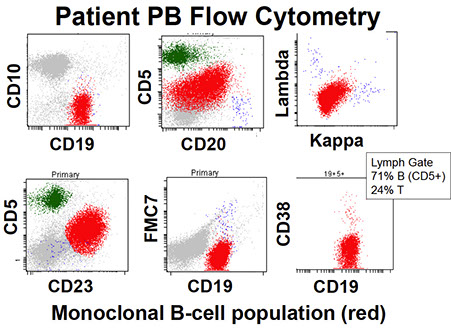

Mature B-cell neoplasms

Chronic Lymphocytic Leukemia/Small Lymphocytic Lymphoma (CLL/SLL)

Monomorphic, mono-/oligoclonoal small round B-lymphocytes in lymph tissue (spleen, LNs), BM, PB which are CD5/23 (+)

- MCC leukemia in adults in Western countries (very low in Eastern countries [= genetically inherited?]); 2:1 M:F ratio; avg age 65 years

- (+) FamHx at least doubles risk of CLL (strongest genetic influence of all B-cell cancers; familial clustering in 1/20; 1st degree relative = 5x baseline risk)

- sx= adenopathy, S-megaly, PB/BM involvement

- autoimmune dz common, (+) DAT in 1/3

- immunodef common; hypogammaglobulinemia in up to 1/2

- sometimes see M protein

Defined as Monoclonal B-cell count > 5 x 109/L in peripheral blood

- Characteristic immunophenotype

- The term small lymphocytic lymphoma is used when there is diagnostic extramedullary involvement and the PB count is < 5 x 109/L

B-cell prolymphocytic leukemia (PLL)

B-cell prolymphocytic leukemia (PLL)

Hairy cell leukemia (HCL)

Indolent cancer of B-cells with "hairy" cytoplasmic projections, oval nuclei and lots of cytoplasm

Splenic B-cell lymphoma/leukemia, unclassifiable

Small B-cell clonal proliferations of spleen that don't fit another category

Lymphoplasmacytic Lymphoma (LPL)

Cancer c small B-cells, plasmacytoid lymphs, and plasma cells often in BM that does not fulfill the criteria for any other small B cell lymphoid neoplasm with plasmacytic differentiation

lgM Monoclonal gammopathy of undetermined significance

(IgM MGUS)

• In 2017 WHO, own distinct entity

- Must distinguish IgM MGUS that may be MYD88 mutated from non-IgM MGUS which does not have MYD88 mutations

• Recognized to be more akin to LPL than to myeloma (unlike IgG and IgA MGUS, which is more similar to plasma cell neoplasms)

• Much less prevalent than IgG and IgA MGUS

_____________________________________

Diagnostic criteria

• Serum IgM monoclonal protein <30 g/L

• Bone marrow lymphoplasmacytic infiltrate <10%

• No evidence of CRAB, constitutional symptoms, hyperviscosity, etc. that could be attributed to lymphoma (lymphadenopathy [LAD])

_____________________________________

Micro: plasma cells and plasmacytoid lymphocytes <10% of the marrow cellularity

- mildly increased plasma cells, usually well-differentiated, clonality can be difficult to detect by IHC (flow cytometry may be helpful in this situation)

- May be impossible to distinguish bwt reactive plasmacuytosis and MGUS

- may appear completely normal!

- requires correlation with clinical data

_____________________________________

IHC: clonal B-cells seen in 75% of IgM MGUS by flow, with a phenotype similar to LPL, plasma cells CD56-

_____________________________________

Genes: Approximately 50% of cases harbor MYD88 L265P mutation; 20% have CXCR4 mutations (also in 30% of LPL, but not in IgG/A MGUS)

_____________________________________

Px: risk of progression is 1.5% per year, goes to LPL/WM, amyloidosis, or other lymphoma

- compare to Non-Igm MGUS, which has1% progression per year to MM, plasmacytoma, amyloidosis

- light chain MGUS has 0.3%/year progession to MM/amyloidsis

_____________________________________

Key tips

• Clonal B-cell component and/or clonal plasma cell component may be difficult to detect

– Low numbers to being with

– Within a polyclonal background

• Assure adequate sensitivity of your MYD88 assay

Evaluation of M protein in BM

MGUS risk of progression [14]